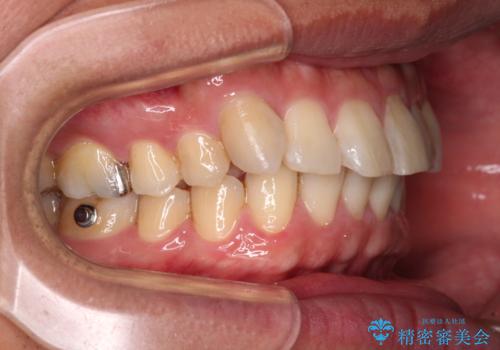

- 矯正装置

- インビザライン

- 治療期間

- 4年8ヶ月

- 治療回数

- 10-30回